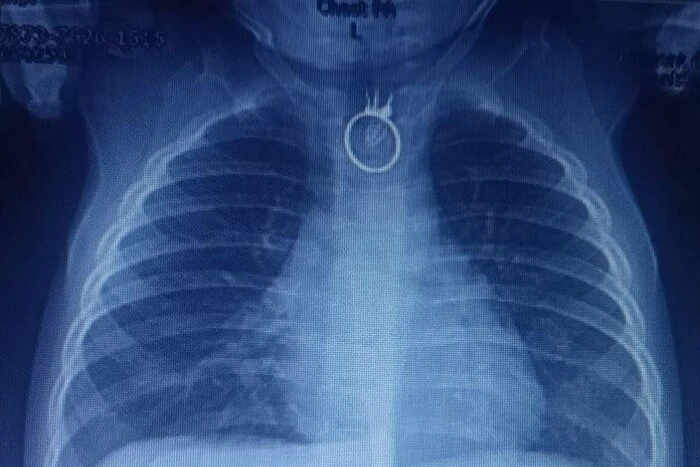

Лікарі Львівської лікарні "Охматдит" врятували 10-місячного хлопчика, який проковтнув іграшковий перстень. Батьки помітили, що син став неспокійним, мав постійну слинотечу, порушення дихання та задишку. Вони зрозуміли, що хлопчик проковтнув сторонній предмет і відразу відправилися до лікарні у Новому Роздолі. Там лікарі зробили рентген, на якому побачили іграшковий перстень. Дитину терміново доставили до Центру дитячої медицини лікарні "Охматдит".

Дитячий хірург Олександр Колодій розповів, що дитину оперували з видаленням перстня. Операція пройшла успішно, хоча перстень трохи пошкодив стравохід. Вже наступного дня хлопчик почав їсти та пити і був виписаний додому після обстежень.